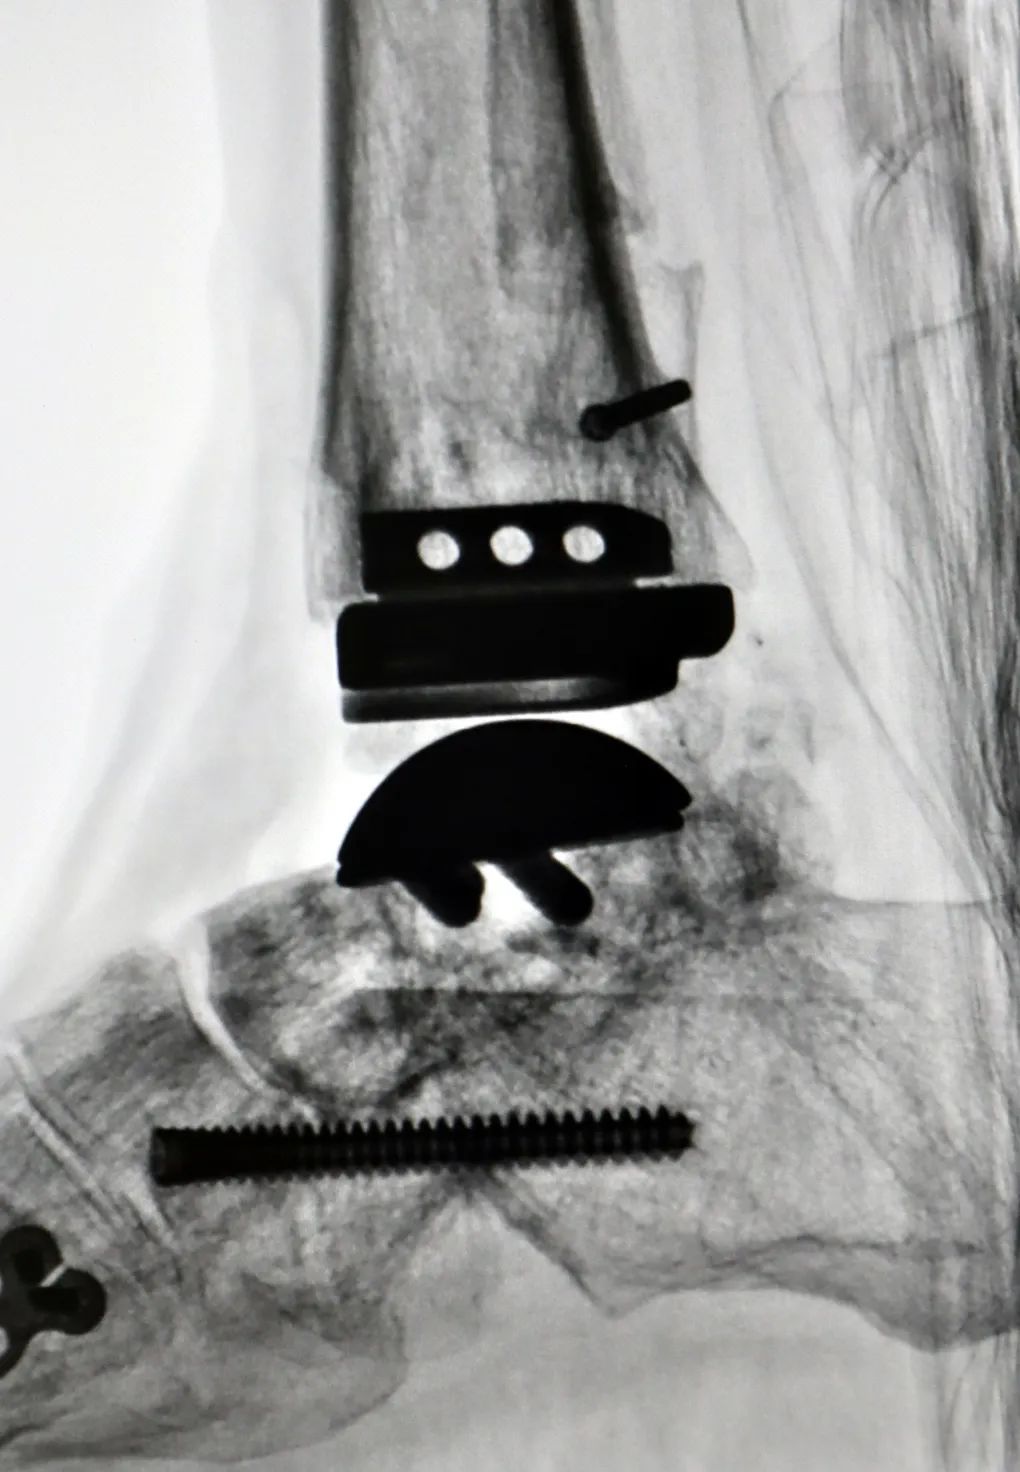

为最大限度提升术后效果,梁晓军为患者进行了全面完善的术前检查和准备。2月28日,肖某玲迎来了手术日。手术打开已经生长在一起的骨头,将原来的内固定取出,重新松解周围软组织、定位踝关节开放截骨线,最后将人工假体成功植入。“融合术后原来的两块骨头就变成一块了,要重新找到关节面,精确打开,再松解周围组织,手术要求非常高,好在手术顺利完成了。”梁晓军说,术后,肖某玲的踝关节就可以重新活动了。